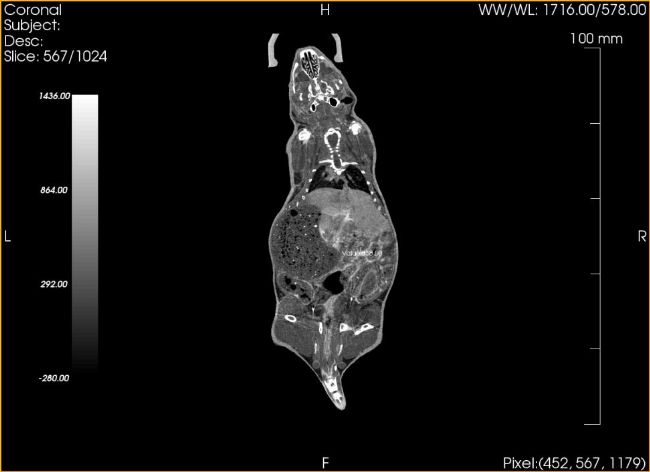

CBCT的一局限性是密度分辨率不夠,對(duì)部分軟組織解剖結(jié)構(gòu)特別是軟組織病變顯像不如螺旋CT清晰。所以,在Micro CT的小動(dòng)物實(shí)驗(yàn)上,一般會(huì)使用造影劑來(lái)增加內(nèi)臟的對(duì)比度。